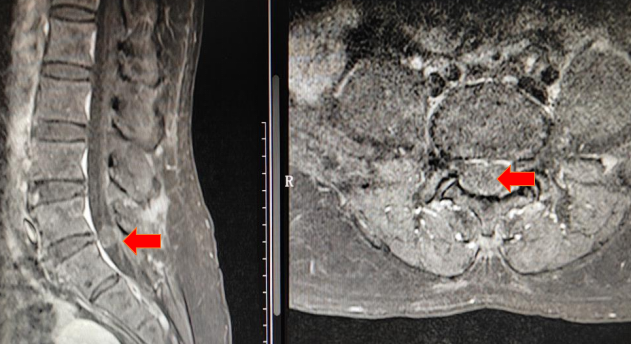

根据MRI检查结果,李女士腰5/骶1椎管内有一个玻璃弹珠大小的肿物,马尾神经严重受压,排除腰椎间盘突出诊断,椎管内肿瘤诊断明确。肿瘤强化不明显,说明肿瘤血运不丰富,跟椎管内胆脂瘤比较相符,但最终需要病理结果证实。目前诊断已基本明确,手术指征也是明确的,它就像一颗定时炸弹,如果不及时拆除,症状随时可能加重,严重者甚至会导致大小便失禁等马尾神经损伤的症状。

腰椎MR/ 提示椎管内巨大肿物压迫马尾神经

腰椎MR增强/ 考虑实质肿瘤,性质待定